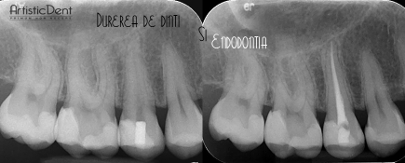

• endodontie